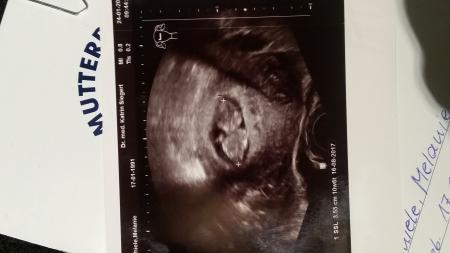

Mit dem Pfirsich ist alles super. Ich bin heute bei 10+6 und der Wurm ist 5,33cm groß. Der ET bleibt jetzt auch beim 16.8. Jetzt bin ich halt am überlegen, ob ich die Nackenfaltenmessung machen soll. Ich weiß nicht (falls wirklich was wäre), etwas an der SS ändern würde. Wie seht ihr das denn?

Bild zu FA-Termin heute - Forum für August - Mamis